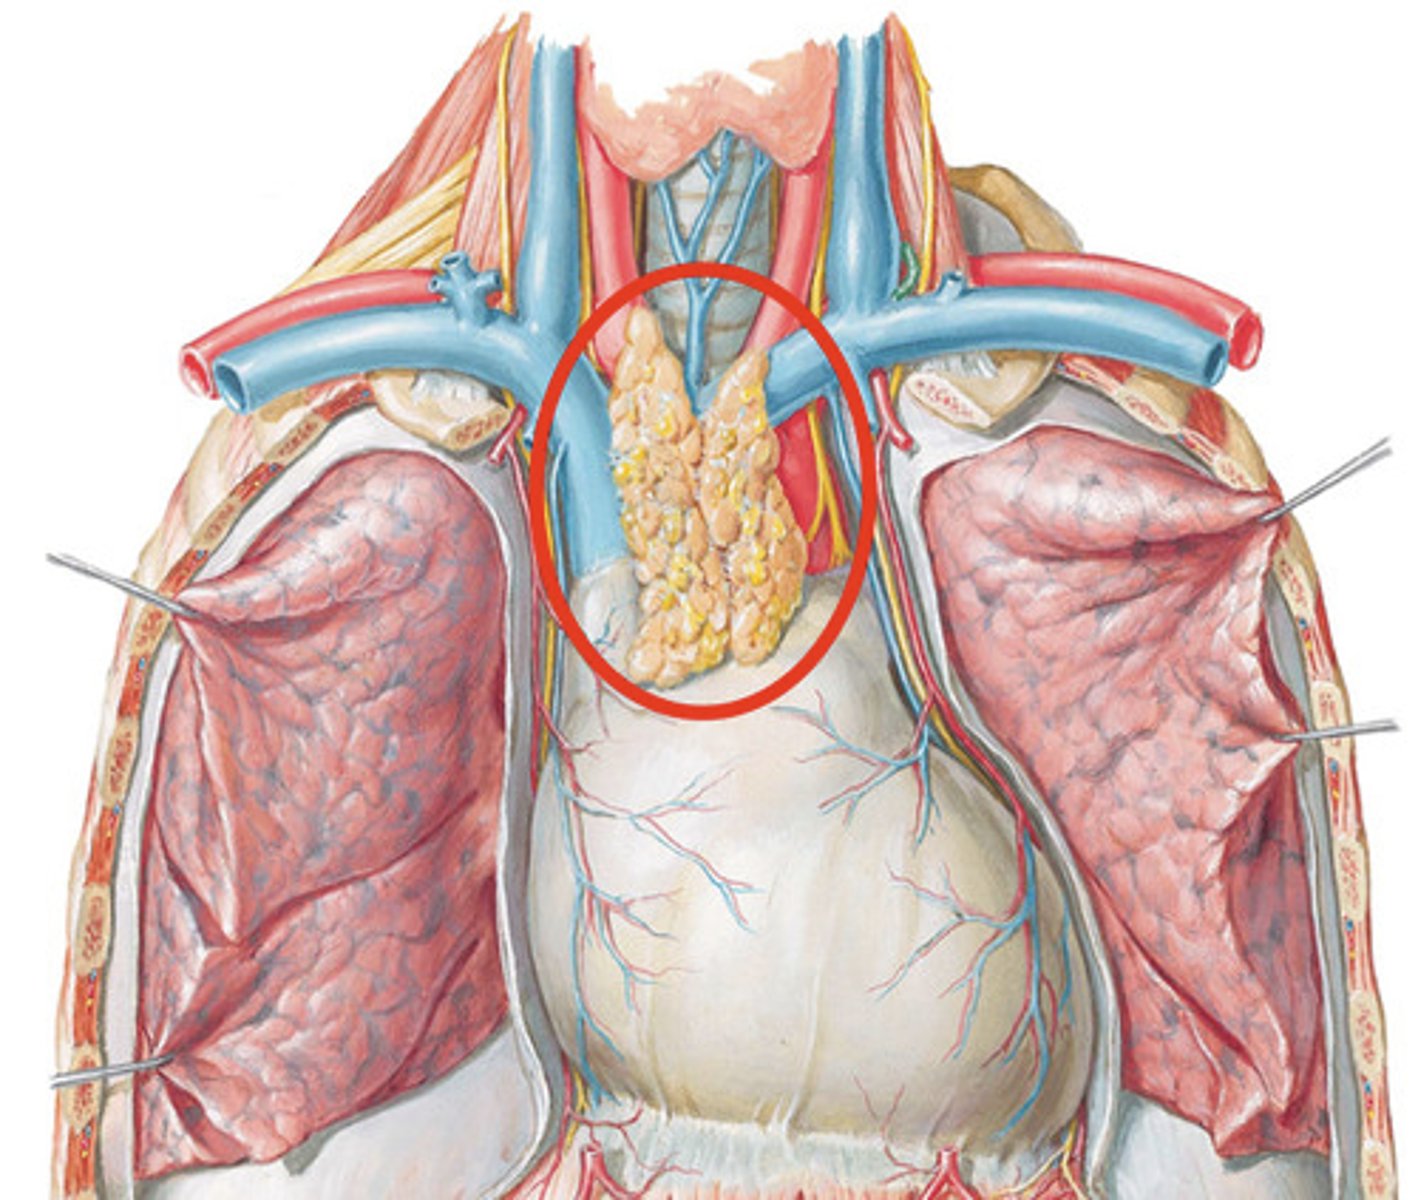

Primary lymphoid tissues

Bone marrow and thymus

What does the thymus do?

Site of T cell differentiation and maturation